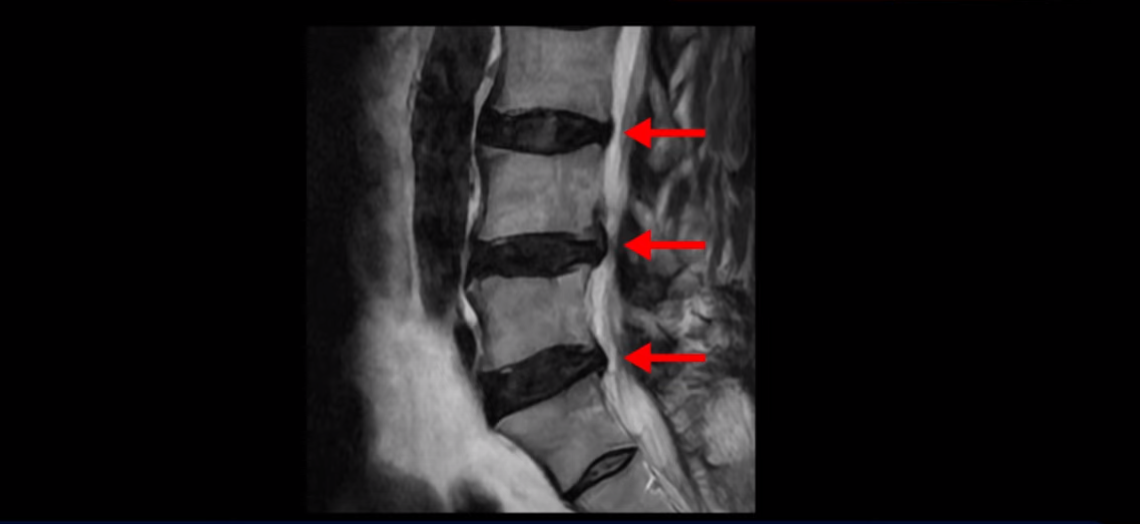

이분 MRI를 보면 허리 세 마디 정도의 퇴행성 디스크가 있고

4번 5번 마디에는 중심성 협착이 있습니다.

후관절과 황색인대가 두꺼워져 있어서 척추관이 좁아져 있습니다.

하지만 이분의 갑작스러운 통증을 일으키는 원인은 4번 5번에 발생한 디스크 파열입니다.